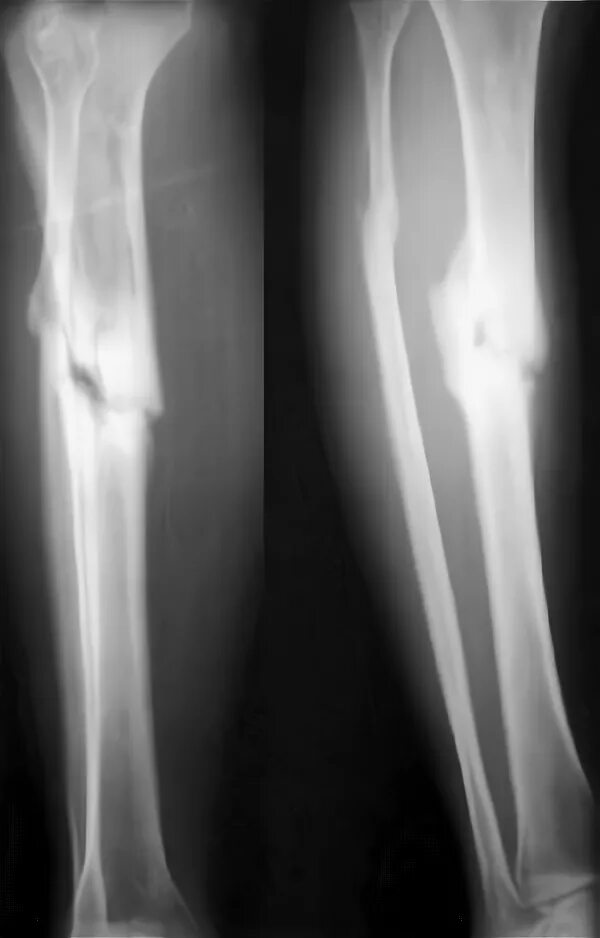

Почему не срастается